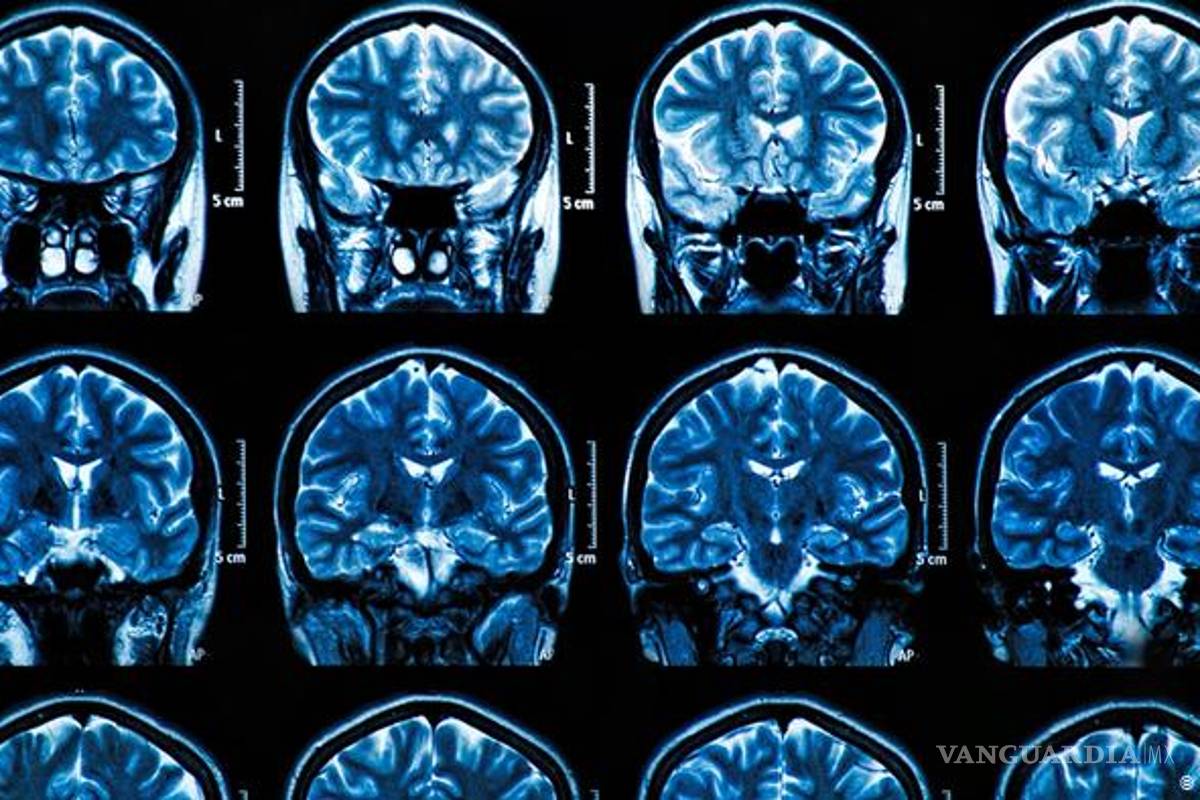

MADRID, ESP.- Un estudio de cómo afecta el COVID-19 al cerebro detectó daños e inflamación en los vasos sanguíneos, que podrían ser consecuencia de la respuesta inflamatoria del cuerpo ante el virus, pues en los tejidos analizados no se hallaron rastros de infección.

Investigadores de los Institutos Nacionales de Salud (NIH) de Estados Unidos analizaron tejido cerebral de 19 fallecidos por la enfermedad, en los que había “sistemáticamente, marcas de daño” causadas por el adelgazamiento y fugas en los vasos sanguíneos.

Sin embargo, no vieron “signos de SARS-Cov-2 en las muestras de tejido, lo que sugiere que el daño no fue causado por un ataque viral directo al cerebro”, según los resultados que publica New England Journal of Medicine.

Los cerebros de los pacientes que contraen COVID-19 “pueden ser susceptibles de daños en los vasos sanguíneos microvasculares” y los resultados “sugieren que pueden estar causados por la respuesta inflamatoria del cuerpo al virus”, según el autor principal del estudio, Avindra Nath, de los NIH.